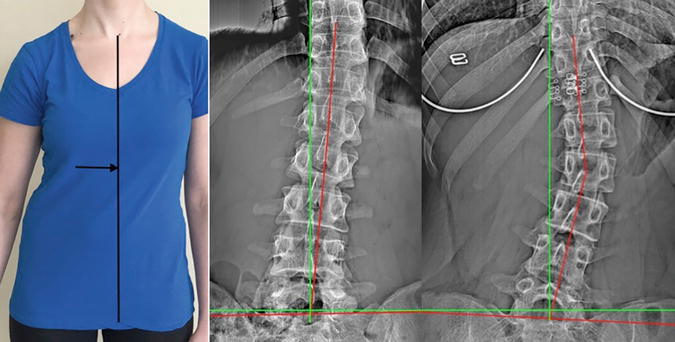

Various examples of structural abnormalities associated with left trunk list as seen on digital radiography (x-ray), green line represents normal alignment, red line represents patient's alignment.

Left shows leg length inequality with structural abnormality, middle shows corrected leg length with lift and persistent structural abnormality, right shows precision structural correction

Image on the left shows a previously undetected anatomical leg length inequality with subsequent rightward torso listing structural abnormality. Image in the middle shows improvement with a 21 mm lift addressing the leg length inequality while the structural abnormality persists. Image on the right shows an excellent structural correction following care. For more information on this case please read:

Woodham T, Fortner M, Oakley P, Harrison D. REDUCING ‘CROOKED’ LATERAL SPINE SUBLUXATION (GLOBAL CORONAL IMBALANCE) IN 5 PATIENTS WITH DEGENERATIVE DISC DISEASE IN THEIR 6TH AND 7TH DECADE OF LIFE: A CASE SERIES INVOLVING CHIROPRACTIC BIOPHYSICS© TECHNIQUE. JCC. 2021;4(1):128-137.